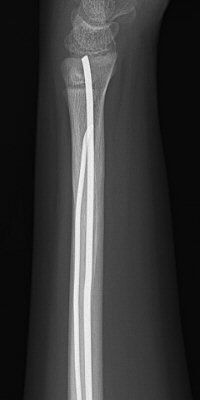

Distala diafysära radius- och ulnafrakturer, opererade med TEN-spikar, sista bilderna läkt efter 7 månader. Alla bilderna är från samma patient.